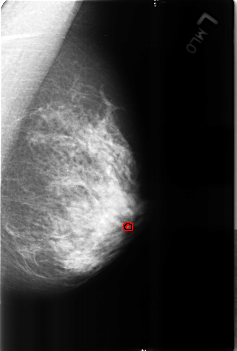

B_3168_1.LEFT_MLO

FILE: B_3168_1.LEFT_MLO.OVERLAY

TOTAL_ABNORMALITIES 1

ABNORMALITY 1

LESION_TYPE CALCIFICATION TYPE COARSE-LUCENT_CENTER DISTRIBUTION N/A

ASSESSMENT 2

SUBTLETY 3

PATHOLOGY BENIGN_WITHOUT_CALLBACK

TOTAL_OUTLINES 1

BOUNDARY